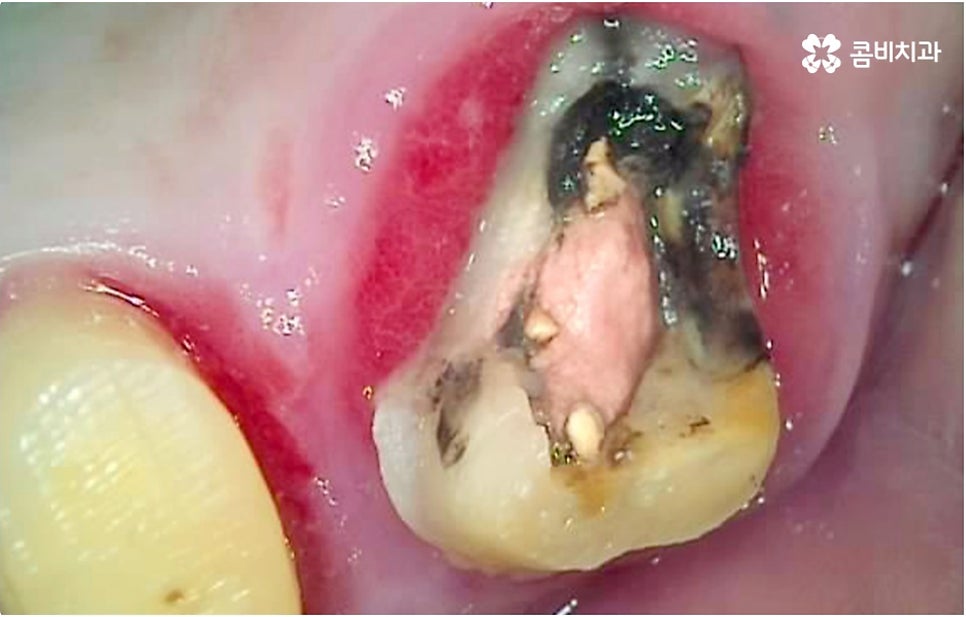

하지만 아직도 두려움이나 또는 일상이 바쁘다는 이유로 더이상 참을 수 없을 정도로 치통이 심해진 후에야 명동치과 에 내원하시는 분들이 있어요. 심한 경우 자연 치아를 살릴 수 없는 상황이 생길 수도 있기 때문에 될 수 있는 대로 시리거나 쑤시는 등 통증이 시작되었을 때 바로 치과로 오셔서 검진 및 치료를 받아보시길 권유드리고 있습니다. 초기에 발견할수록 통증도 적고 치료를 할 때 시간적인 부담이나 비용적인 부담도 줄어드는 것이 사실이나 충치 초기 법랑질에만 손상이 있을 때는 통증이 없고 잇몸 질환 역시 심해질 때까지는 크게 아프지 않기 때문에 자각 증상에만 기대기에는 한계가 있어서 정기적인 검진이 대단히 중요하다고 말씀을 드린 거예요.

자연 치아를 살리기 위한 거의 마지막 단계의 보존 치료가 바로 신경치료, 재신경치료, 치근단절제술 등이며, 만약 치아재식술을 통해서도 살릴 수 없을 정도로 손상이 깊고 심하다면 해당 치아를 발치하고 임플란트를 통해 인공 치아로 대체해 줄 필요가 있습니다.